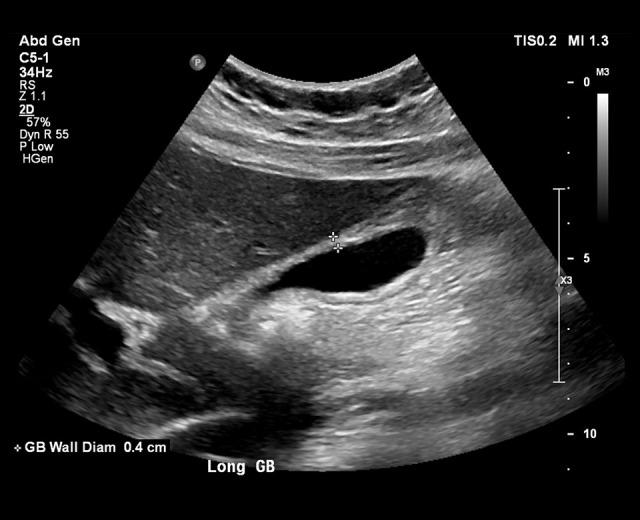

BACKGROUND Infectious mononucleosis secondary to Epstein-Barr Virus is a common infection in young adults. Infection usually involves a self-limiting course of fevers, sore throat, malaise, and myalgias. Transaminitis is a relatively common complication; clinical jaundice, however, is rare. This case report highlights an uncommon complication of Epstein-Barr Virus infection in which hepatocellular injury led to clinical jaundice as well as radiologic evidence of gallbladder pathology mimicking acute calculous cholecystitis. CASE REPORT A 17-year-old girl with no prior medical history presented to our Emergency Department 1 week after being diagnosed with infectious mononucleosis. She was hemodynamically stable and her physical exam was notable for scleral icterus with right upper quadrant tenderness and positive Murphy's sign. Multiple imaging modalities performed showed gallbladder wall thickening without common bile duct dilatation. A hepatobiliary iminodiacetic acid (HIDA) scan showed evidence of hepatocyte dysfunction with normal gallbladder filling. The imaging results obtained in conjunction with her laboratory testing and active infectious mononucleosis infection confirmed the patient's presentation was a result of her Epstein-Barr virus infection and did not require surgical intervention for cholecystectomy. CONCLUSIONS This case report highlights a rare complication of Epstein-Barr Virus infection and demonstrates the utility of interpreting hepatic function testing in conjunction with relevant imaging modalities in cases of clinical jaundice. By doing so, we were able to conclude the patient's gallbladder pathology was related to acute acalculous cholecystitis (AAC) and did not warrant surgical intervention. The patient was given supportive care measures and made a full recovery.

一名无既往病史的 17 岁女孩在诊断为传染性单核细胞增多症后 1 周就诊于我院急诊科。她血流动力学稳定,体格检查可见巩膜黄疸,右上象限压痛,墨菲氏征阳性。多种影像学检查显示胆囊壁增厚,无胆总管扩张。肝胆闪烁显像显示存在肝细胞功能障碍的证据,胆囊充盈正常。结合实验室检查和活动性传染性单核细胞增多症感染获得的影像学结果,证实患者的表现是由 Epstein-Barr 病毒感染引起的,无需进行胆囊切除术的手术干预。